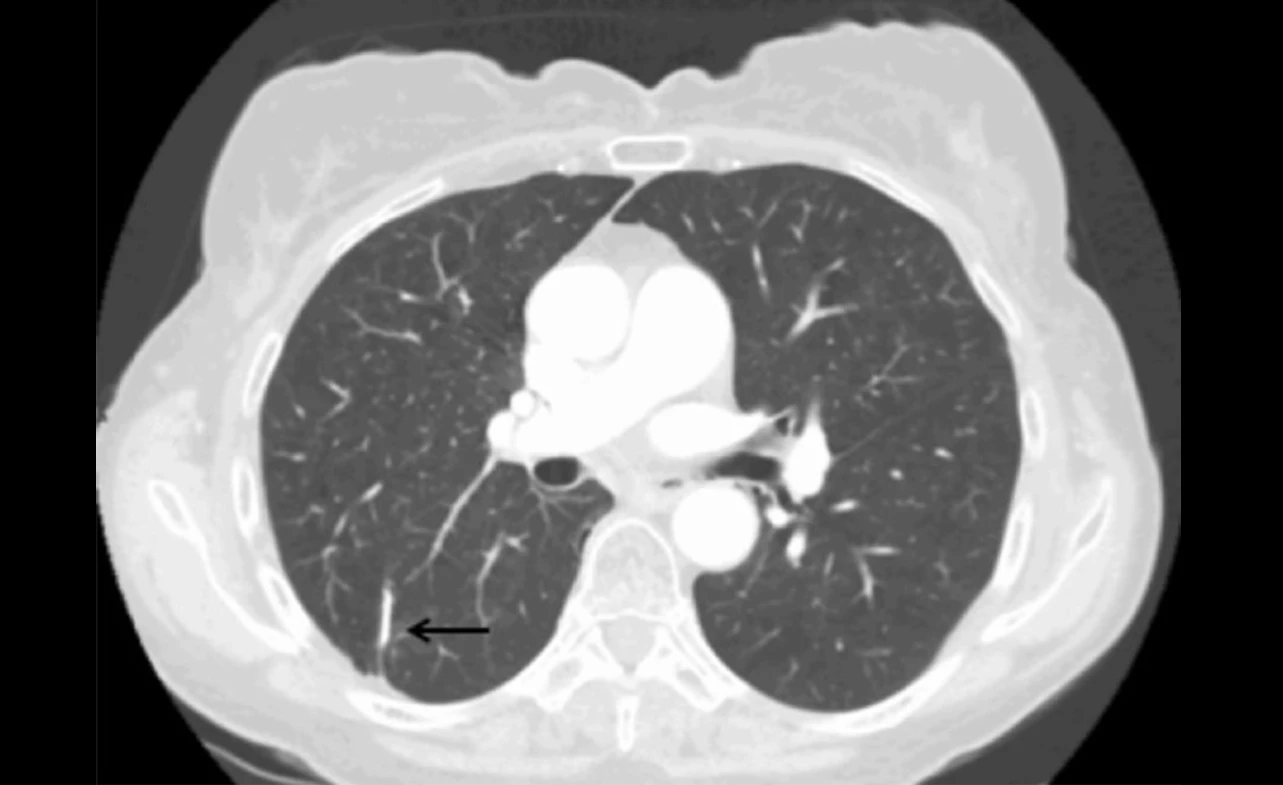

When lung metastasis is suspected in patients with esophageal cancer, diagnostic tests play a critical role in confirming the spread to the lungs. These tests help healthcare professionals make an accurate diagnosis and formulate an appropriate treatment plan based on the extent of the metastasis. Let’s explore some of the commonly used diagnostic tools for identifying lung metastasis from esophageal cancer:

Imaging Tests

Imaging tests are typically the first step in evaluating lung metastasis. They allow doctors to visualize the lungs and identify any abnormal growths or masses. Common imaging tests used for this purpose include:

• Computed Tomography (CT) scan: Provides detailed cross-sectional images of the lungs, enabling doctors to detect the presence of metastases.